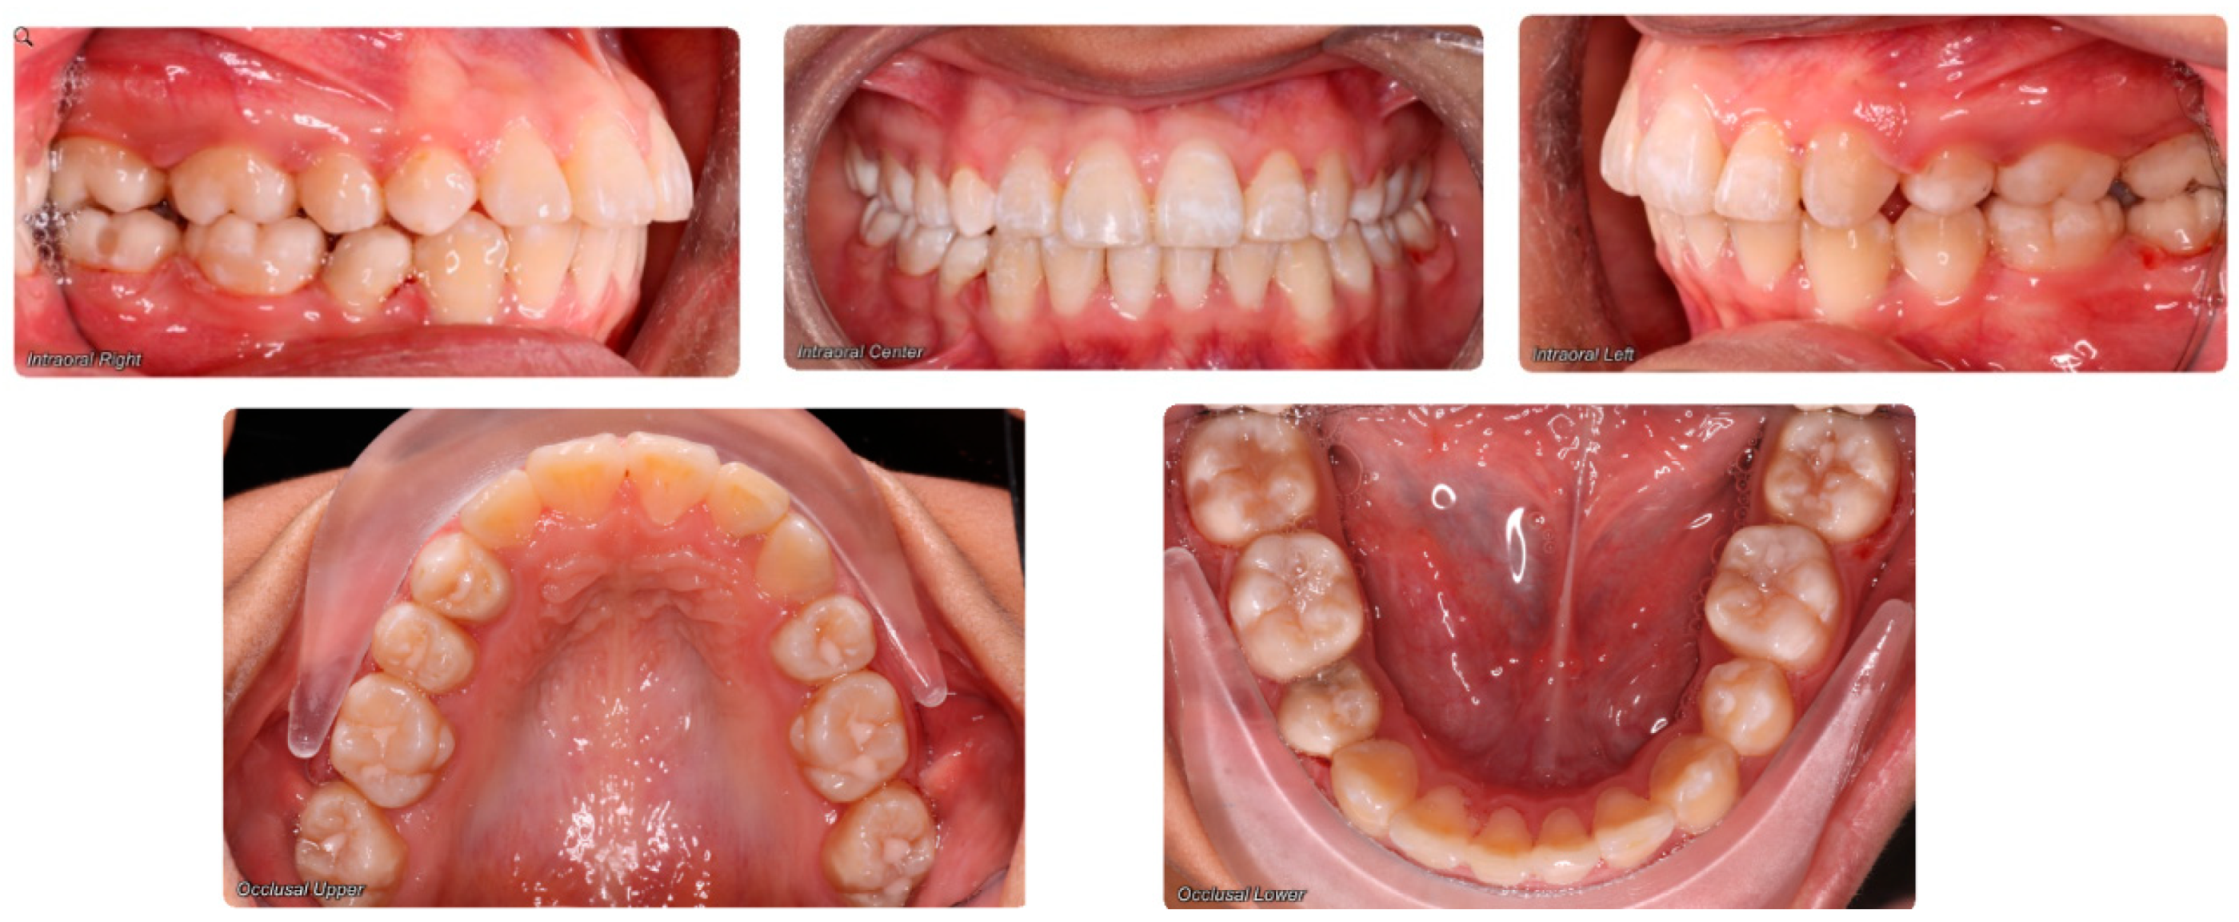

- Evaluation of buccal and lingual cortical plates: Figure 5, Figure 6 and Figure 7 show a case in which the mandibular lateral incisors are positioned lingual to the central incisors. Both mandibular lateral incisors are adjacent to each other. Figure 5 shows and intraoral occlusal photos with retained deciduous mandibular lateral incisors. There was no way to evaluate the buccal and lingual cortical plates through conventional 2D panoramic, periapical or occlusal radiographs. Therefore, CBCT was acquired and collimated to the area of teeth in order to assess the relationship of the four mandibular incisors to the labial and lingual cortical plates as well as to the adjacent teeth. As Figure 6 and Figure 7 display, CBCT shows that all permanent mandibular incisors are sound. It is important to note that thin buccal and lingual cortical plates may not be seen via CBCT—this does not denote that they are not present. In other words, CBCT images may not show a clinically present thin buccal and lingual cortical plates. In this case, the diagnostic information obtained from CBCT is far more significant than the information obtained from any other radiographic imaging technique.